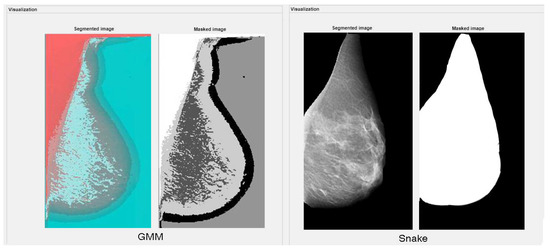

3.2.8. Gaussian Mixture Model

3.2.6. Active Contour Models: Snakes

4.3. Performance Analysis